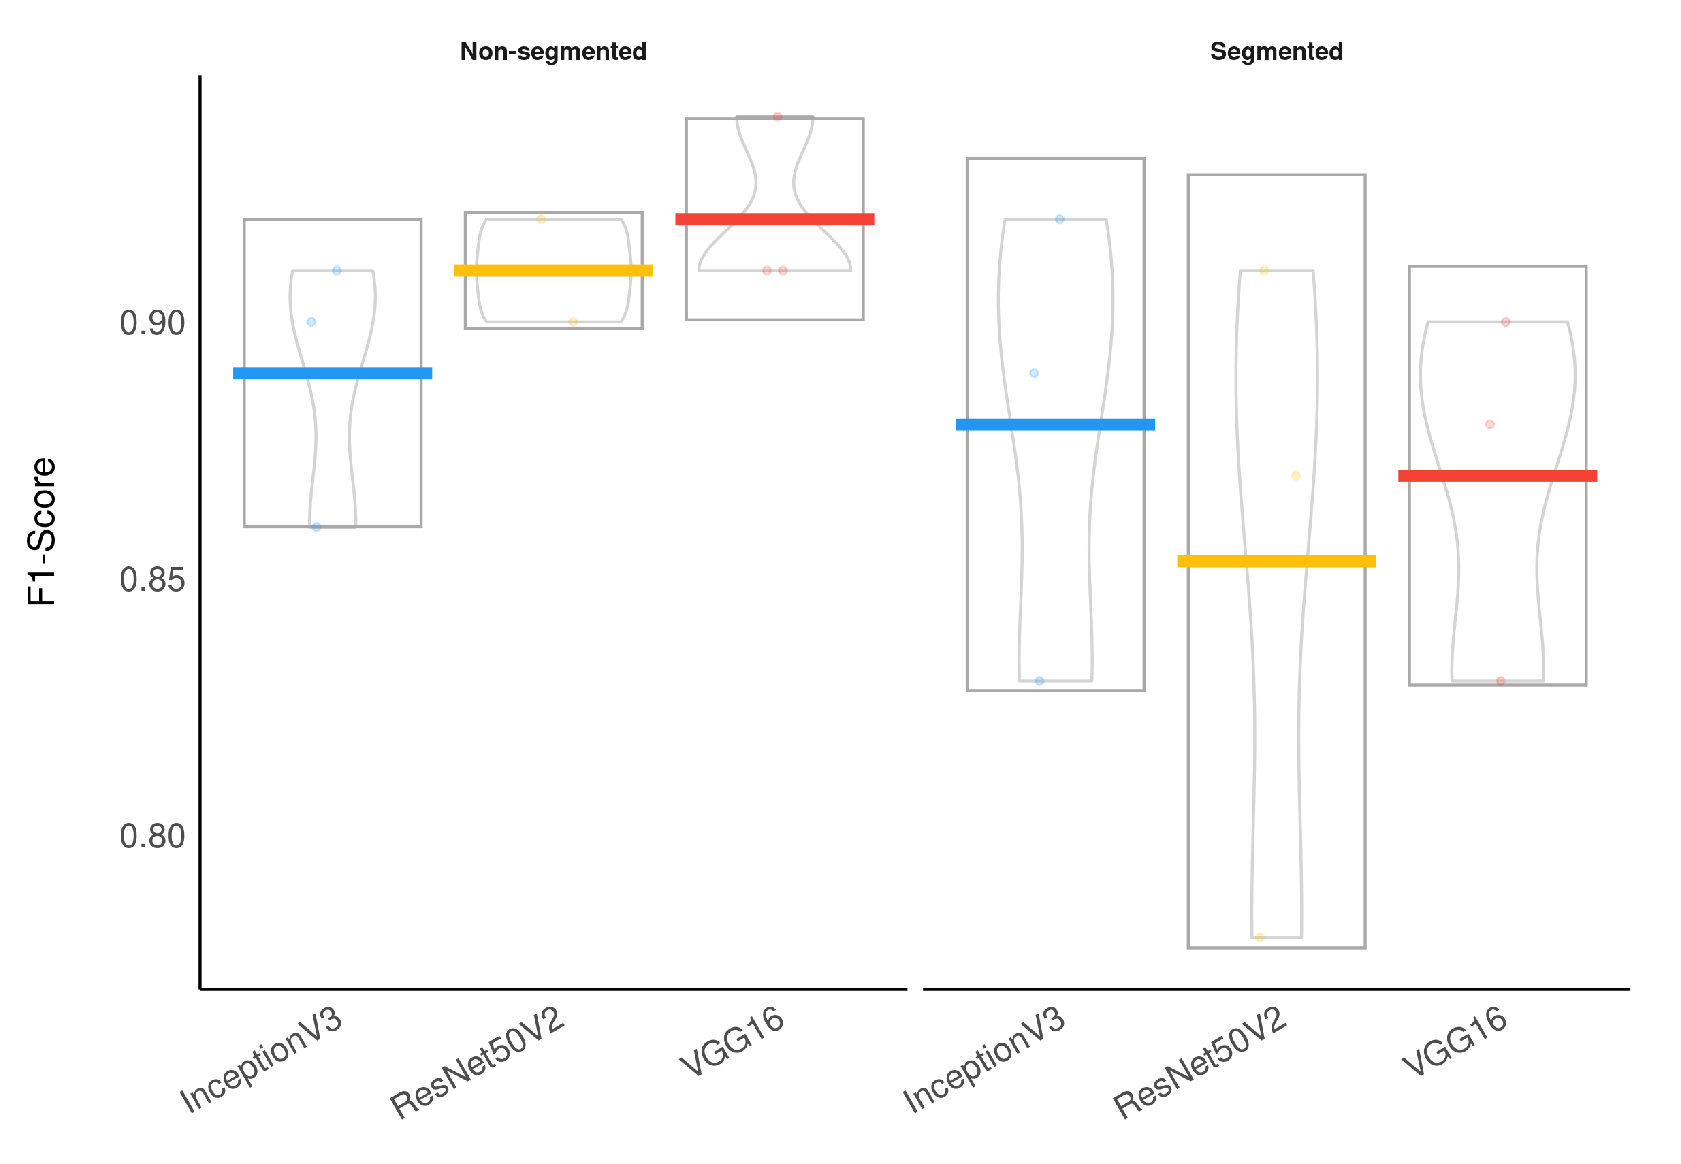

To evaluate the segmentation impact on classification, we applied a Wilcoxon signed-rank test, which indicated that the models using segmented CXR images have a significantly lower F1-Score than the models using non-segmented CXR images (

Figure 12 presents a visual representation of our classification results stratified by lung segmentation with a boxplot.

In general, models using full CXR images performed significantly better, which is an exciting result since we expected otherwise. This result was the main reason we decided to apply XAI techniques to explain individual predictions. Our rationale is that a CXR image contains a lot of noise and background data, which might trick the classification model into focusing on the wrong portions of the image during training.

Considering specifically the models using segmented CXR images, InceptionV3 performed better in all classes.

Figure 14 provides a visual representation of the F1-Score achieved in the experimental results stratified by the model used and lung segmentation.